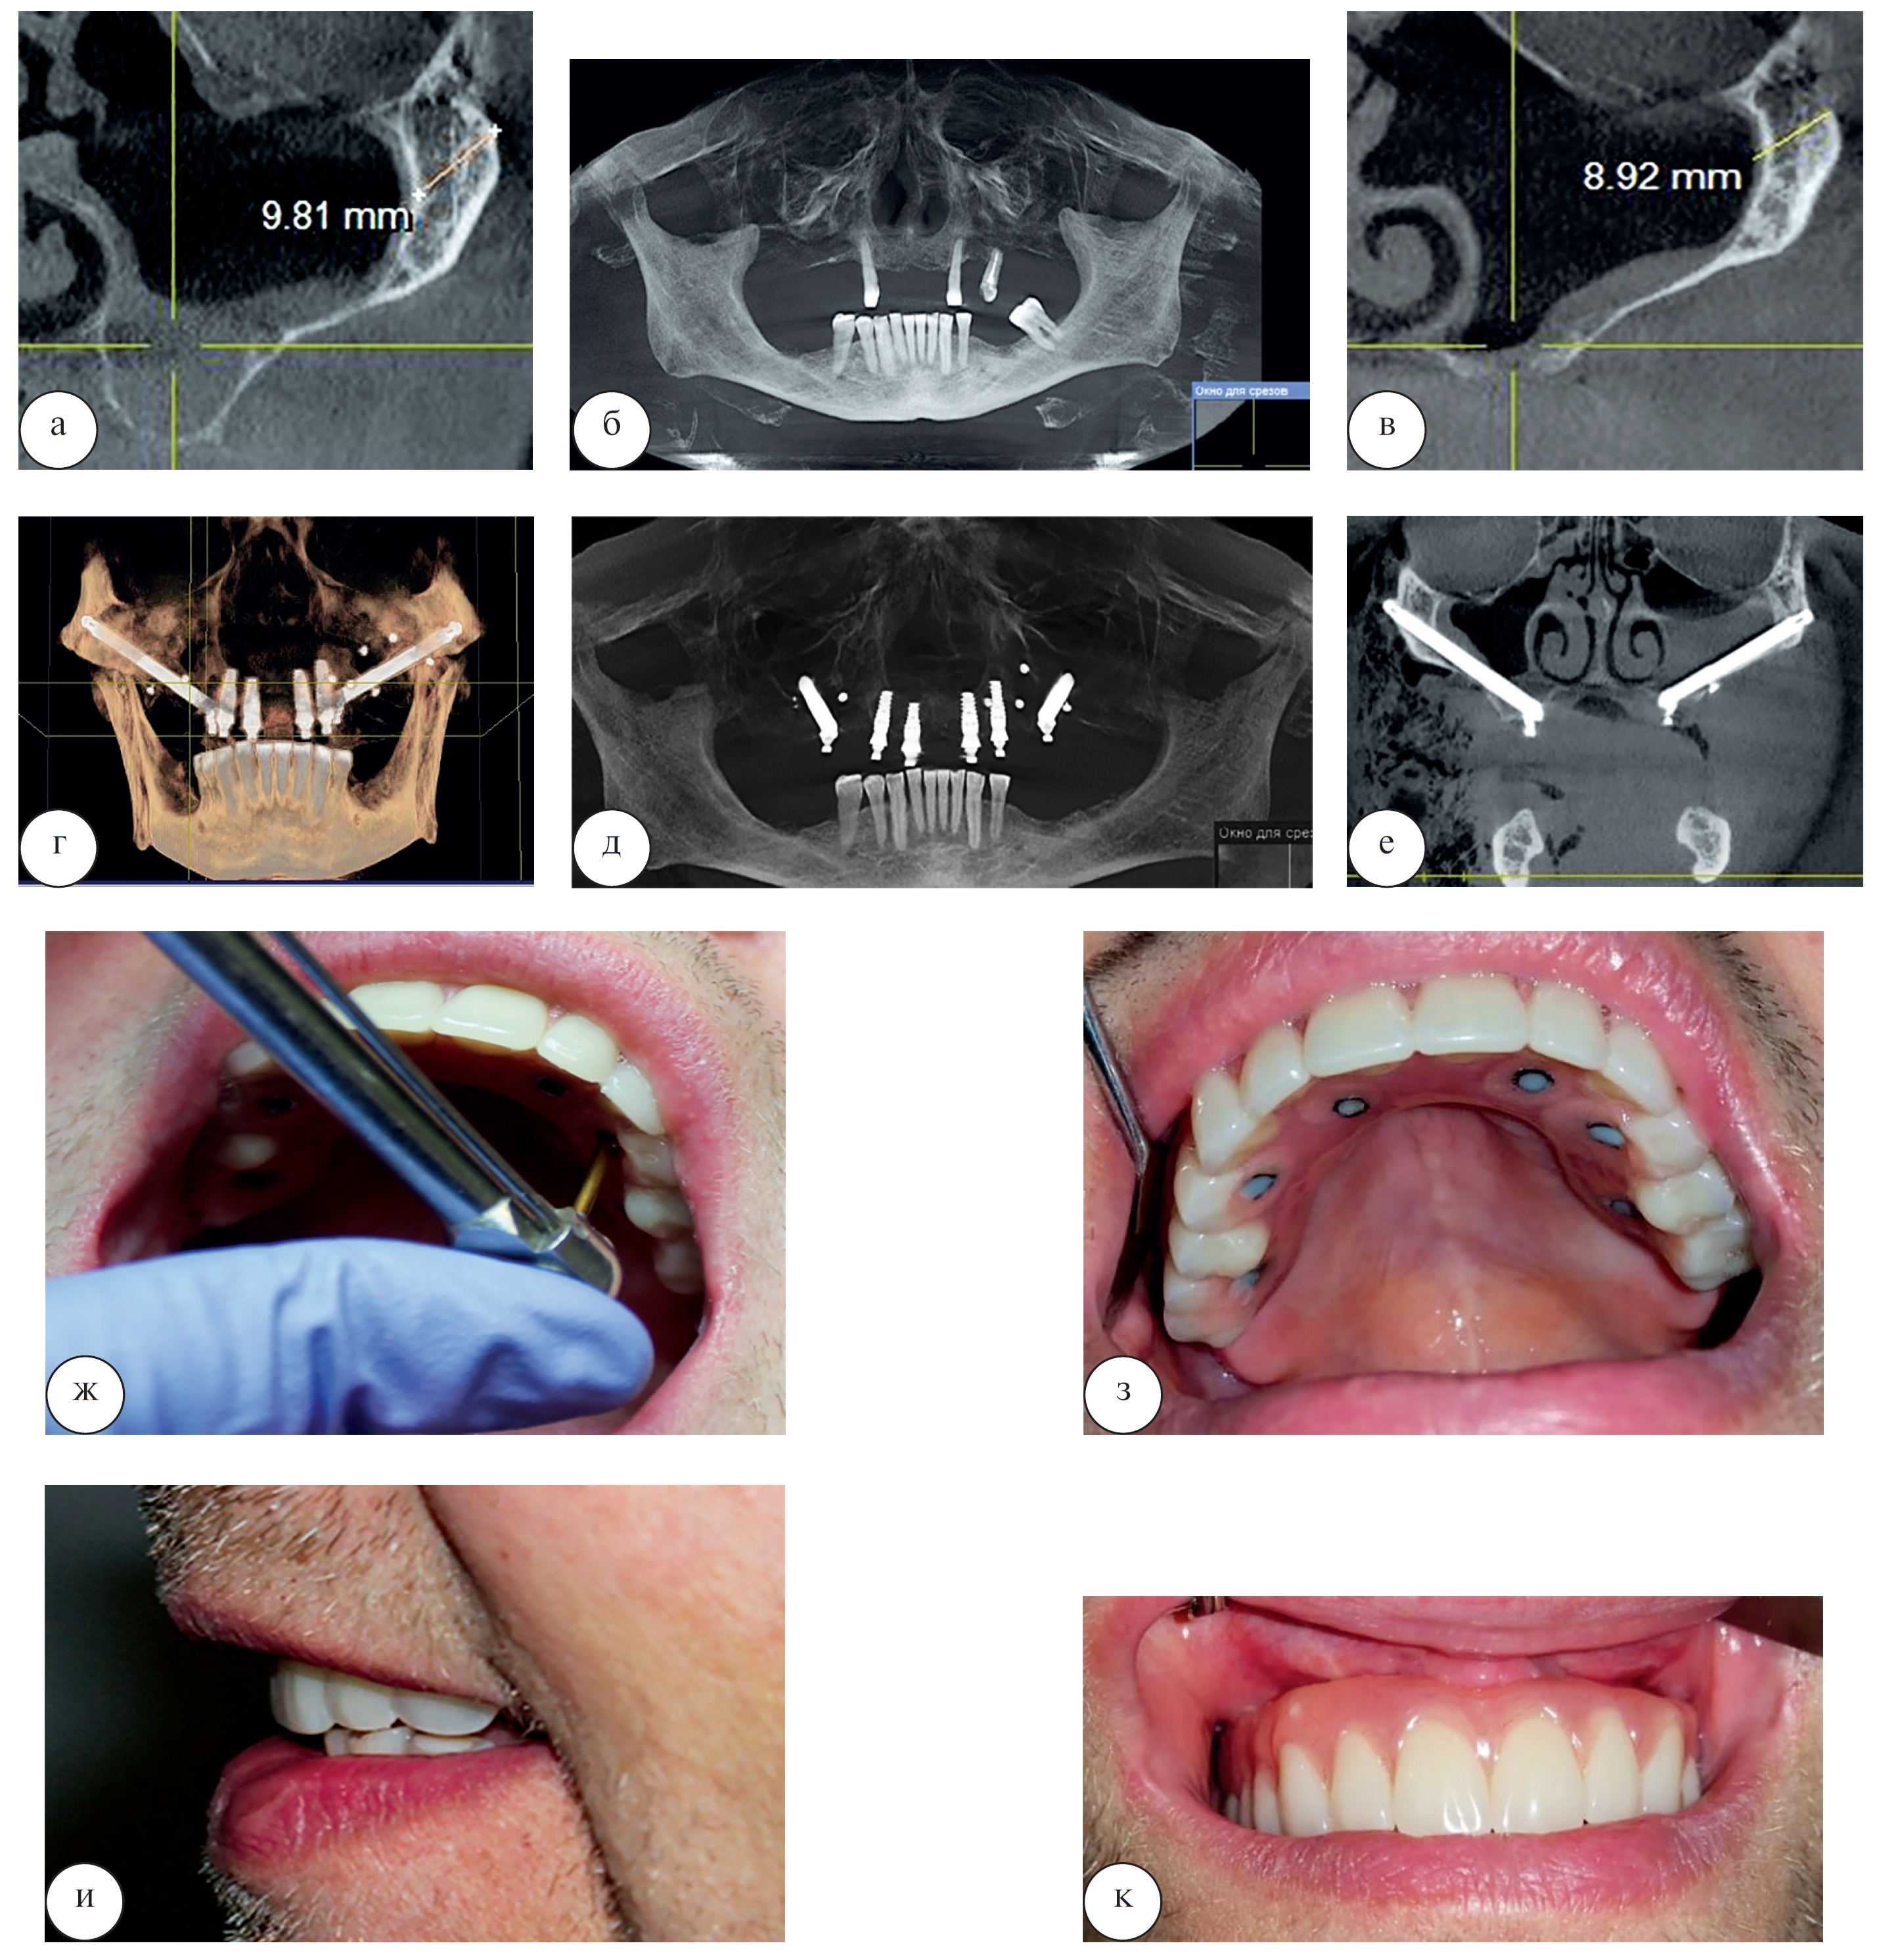

Безусловно, данная методика имеет свои положительные стороны, она позволяет осуществить стоматологическую реабилитацию быстро и без применения костнопластического материала. Но и не лишена своих недостатков: методика крайне сложна в исполнении, для ее исполнения необходима высокая квалификация челюстно-лицевого хирурга, требует проведения операции под общей анестезией, может быть сопряжена с большим количеством осложнений, чем предыдущий метод [1, 17]. Клинический пример стоматологической реабилитации пациента Х. 58 лет с использованием скуловых имплантатов представлен на рисунке 13.

Рис. 13. Стоматологическая реабилитация пациента Х. 58 лет с использованием скуловых имплантатов: а, б, в – срезы компьютерной томограммы до начала лечения; г, д, е – срезы компьютерной томограммы после лечения; ж – фиксация условно-съемного протеза в полости рта через 24 часа после операции; з – вид ортопедической конструкции в полости рта; и, к – контрольный осмотр через 2 года после завершения лечения

При выполнении диагностической компьютерной томографии у пациента была диагностирована выраженная атрофия альвеолярного отростка верхней челюсти. Толщина костной ткани в области альвеолярной бухты верхней челюсти составляла не более 2 мм. Во фронтальном отделе объем костной ткани также был недостаточен для реализации классического протокола на 4 дентальных имплантатах. Под общей анестезией было проведено оперативное лечение с установкой 2 скуловых имплантатов и 4 дентальных имплантатов, фиксация условно-съемного протеза была осуществлена через 24 часа после операции. Конструкция окончательного протеза для пациента чаще всего изготавливается из акриловой пластмассы на балке или из металлокерамики, но по желанию пациента возможно использование других дорогостоящих материалов – диоксида циркония или металлокомпозита.